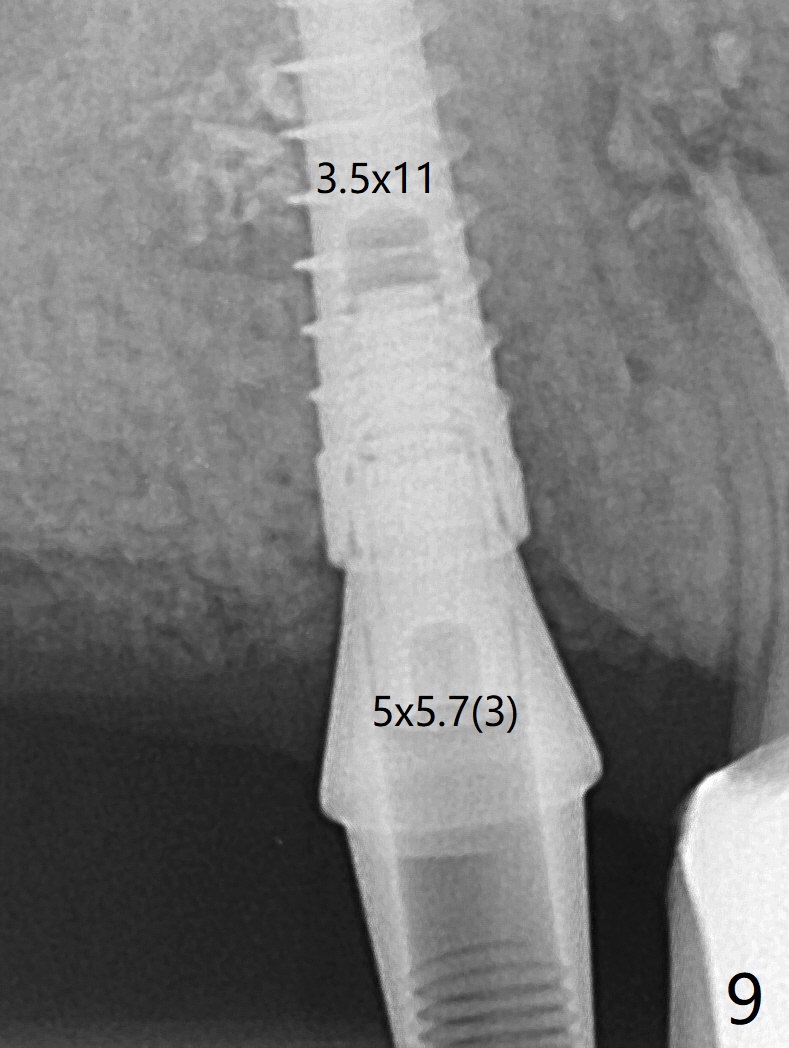

The patient returns for #4 extraction and immediate implant the 1st day clinic reopening after coronavirus lockdown. To reuse autogenous bone for #4 buccal gap closure, delayed implants are also placed at #13 and 14. It is much easier to determine the placement level of the immediate implant (open socket) with guide than that of the delayed ones (flapless) clinically. Immediate postop CT is taken for implant placement level confirmation (Fig.1-3). In fact the autogneous bone is too soft to be packed into #4 socket gaps. It has to be mixed with allograft to be packable. There is oozing when #14 healing abutment is placed. The hemorrhage is severe 4 days postop. The healing abutment is replaced by a healing screw. Hemostasis is achieved when the access is closed with GEM Cap and 4-0 Chromic gut suture. The patient will return for #3 extraction and socket preservation 1 month postop (Fig.4). To prevent postop hemorrhage, a cemented or temporary abutment will be placed at #4 before anesthesia, while .5 or 1.0 cc Augma bone will be placed at #3, covered with collagen plug and acrylic. In fact he cancels the appointment once because of symptom relief and will return 2 months postop. Sticky bone (Fig.5 *) and PRF is used at #3 for hemostasis, while a 5x5.7(3) mm pair (final) abutment is used to hold acrylic dressing in place. The latter remains in place with good oral hygiene 1 month postop (Fig.6 A: abutment). When the acrylic dressing is removed, the socket heals (Fig.7 K: the gingiva between the buccal and palatal sockets when the tooth was removed). The patient returns for impression 4.5 months postop. When the 5x5.7(3) mm abutment at #4 is reseated after cleaning, there is no horizontal gap between the abutment and implant in BW (Fig.8), while there is in PA (Fig.9). When a smaller abutment is seated (Fig.10), there appears to be a horizontal gap, whereas there is no vertical one. The situation is the same with #13 (Fig.11,12). The common denominator is 3.5 mm implant. With suspicion, BW is taken for the implant at #4 immediately before cementation (Fig.13). It appears that the abutment is most likely seated completely. There is no bone loss or screw loosening 4 months post cementation (Fig.14,15). One month later the patient agrees to have 3 lower implants to replace RPD.